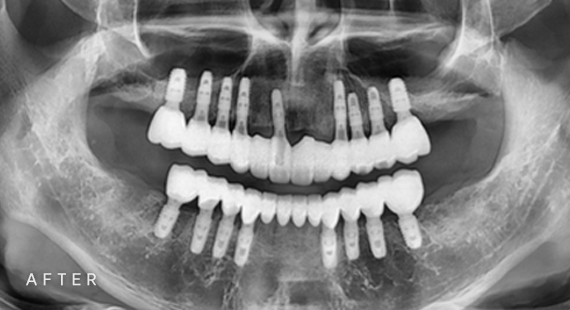

임플란트